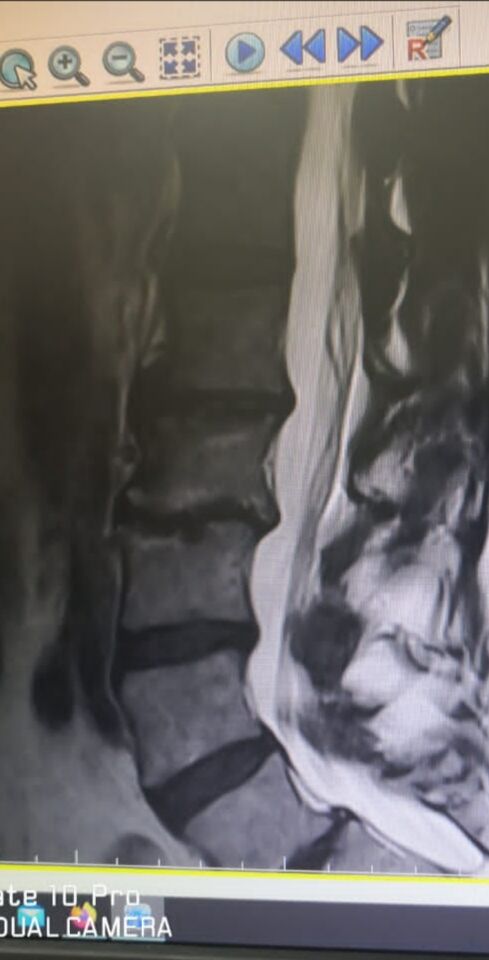

Saya di diagnosed sebagai pesakit Osteoarthritis sejak 2014. Dr beritahu umur tulang saya 16 tahun lebih tua dari usia semasa . Akibatnya

right hip dan left knee saya terpaksa ditukar pada 2019 & 2020 .

Disc pada tulang lumbar juga kian nipis dan hampir habis. Dr cadangkan pasang besi

23 Mei 22 lepas sepatutnya kena cucuk pada L3L4 untuk kurangkan sakit sebab saya tak mahu bedah tulang belakang.

Dalam waiting bay OT Dr and team datang bertanya dan evaluate lagi.

Last question was, sekarang ni tahap sakit berapa? (skala 1-10). Saya jawab 3-4.

Dr terkejut. Kalau 4 kita tak payah buatlah puan! Sebab dulu puan mengadu 7-8. Rawatan ni bertujuan kurangkan sakit kepada tahap 4.

Sejak bila rasa kurang ni? Apa yang puan buat untuk kurangkan sakit. Ada buat senaman ke?

Saya rasa sakit berkurangan banyak sejak akhir April 2022. Saya buat kerja rumah and aktiviti harian biasa saja. Tapi saya ada makan supplement dari Thanks Ai sejak 2 bulan lepas. (Mineral powder, mineral liquid , Joyfil, Profil n Joegenex.) Without fail, i consume day Nite 1 sache each

Bulat mata Dr Apa nama supplement? Takut ada ste.ro!d. Saya maklumkan Joyfil dan Profil dari Thanks Ai. Takda ste.ro!d. Ada proteoglycan yang bantu bina semula rawan.

Masing-masing terus Google cari. Takda ste.ro!d. Tapi tak pernah dengar nama produk.

So saya dilepaskan dari jarum panjang.

Cuma kena datang lagi bulan 9 untuk re evaluation.

Sementara tu mesti buat fisio dan senaman dengan tekun supaya semakin sihat.

Syukur Alhamdulillah.

Sebenarnya saya sangat takut risiko rawatan itu. Sekarang cuba biasakan jalan tanpa tongkat pula. Saya mula yakin dan terus bersemangat untuk rawat diri supaya kuat dan boleh berjalan seperti biasa tanpa tongkat disisi

Supplements Thank Ai tetap diteruskan sebab dah dapat kesan positif. Syukur alhamdullilah. Saya sangat sarankan kepada anda diluar sana yang ada masalah seperti saya mencuba product dari Thanks Ai